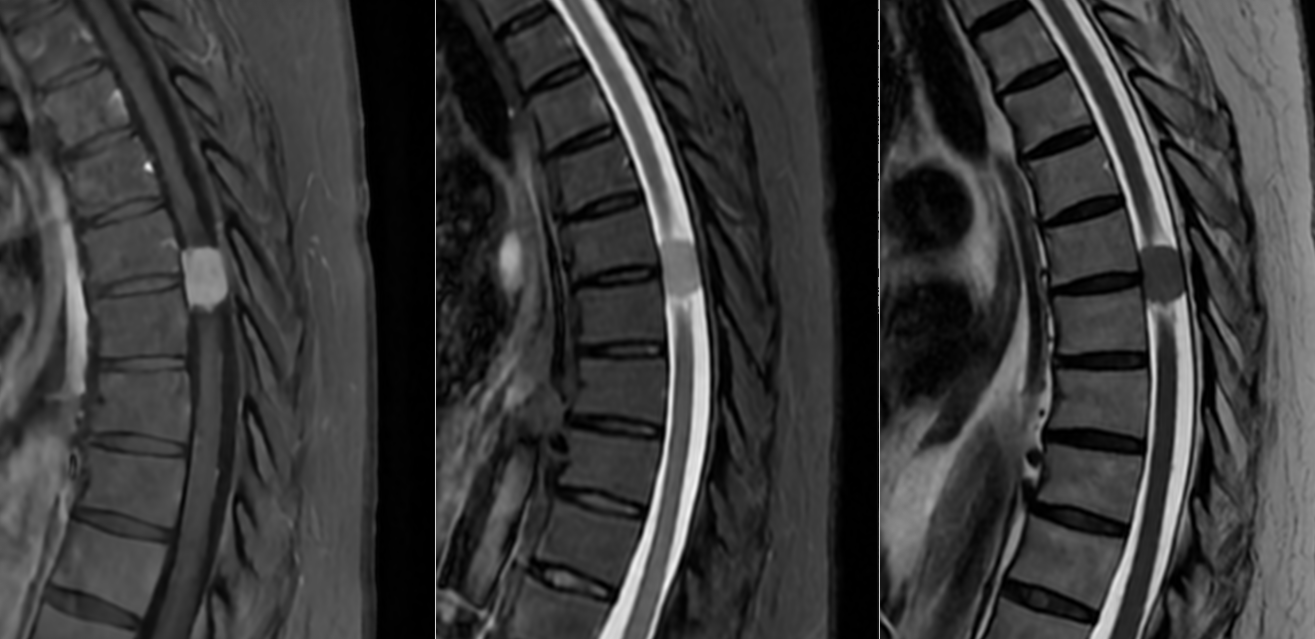

- Măduva cervicală sau toracală – meningioame spinale.

- RMN – cea mai completă investigație, oferă detalii despre relația cu țesutul cerebral, vasele de sânge și nervii Captarea substanței de contrast este deosebit de importantă.